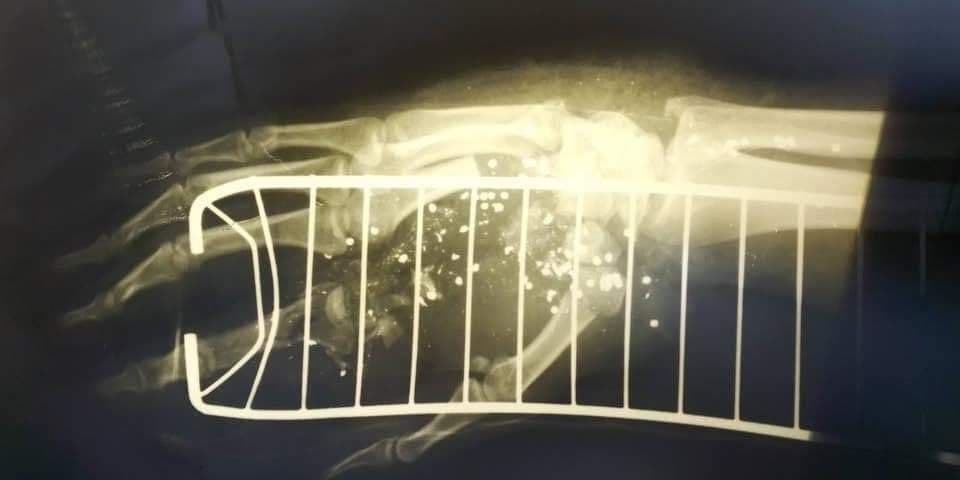

Киевский полицейский, которого ранил пьяный "голосеевский стрелок", мог лишиться кисти левой руки, настолько она была раздроблена зарядом картечи.

Министерство внутренних дел опубликовало несколько жестоких фото, на которых можно увидеть, как выглядела верхняя конечность патрульного Сергея до и после операции. Руку пришлось буквально собирать по частям.